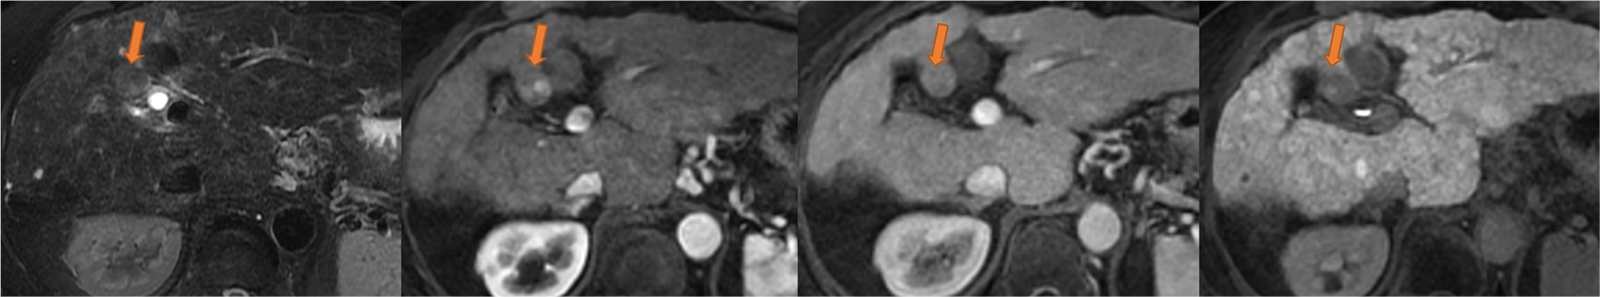

図3.46ヶ月後のEOB-MRI画像(左から脂肪抑制T2強調画像、動脈相、門脈相、肝細胞相)

S4病変は膨張性増大とともに、内部にnodule-in-nodule様の早期濃染やT2WIで高信号域が観察される(矢印)。